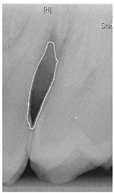

To ensure that only the area framing the symptom is preserved, and to remove the rest of the interfering areas or lines, the symptom frames are extracted according to the closure algorithm, i.e., the maximum connectivity area can be preserved to remove the frames of the non-symptomatic areas, as shown in Figure 7b. After the closure process, some of the frame lines are less smooth than others, which may affect the discrimination accuracy. To deal with this situation, this study performs the filling of the frame lines at the symptom area to facilitate the training of the model. Black and white are chosen to highlight the contrast and to compare the difference in discrimination between the two fill colors, as shown in Figure 7c,d.

Figure 7. Comparison of extracting the closed area and filling. (a) Close operation. (b) Extracting the closed area. (c) Filling with white. (d) Filling with black.